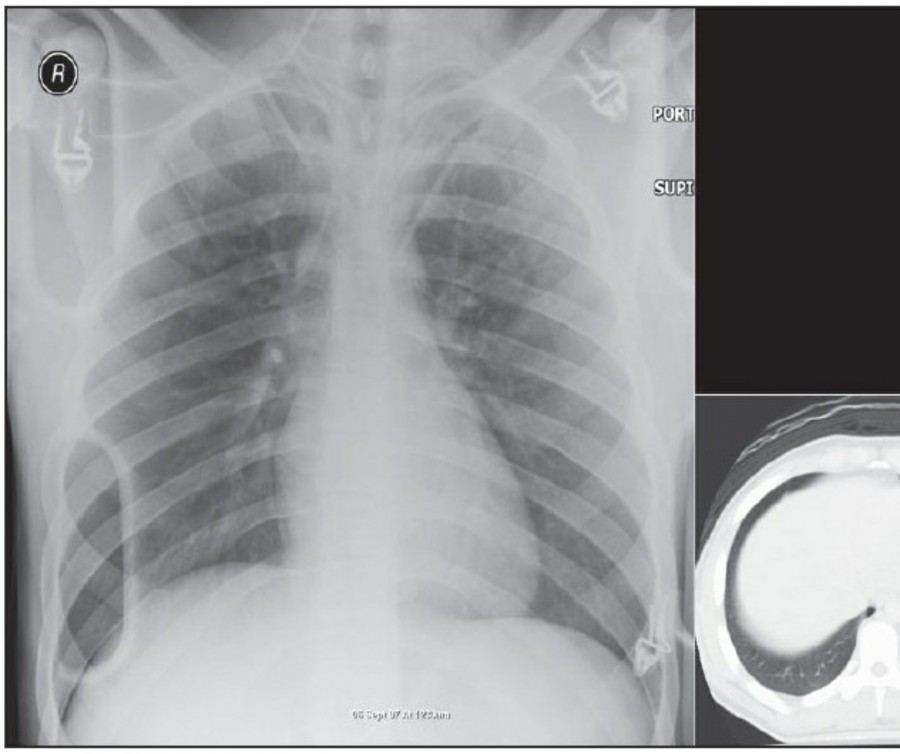

Pneumothorax

공기는 nondependent position으로 위치하므로, X ray상에서는 환자 자세에 따라 다르게 나타난다. Erect position에서 공기는 lung의 apicolateral surface에 위치하고 얇고 하얀 pleural line이 나타나며 그 뒤로 lung marking이 보이지 않는다.

하지만 pleural line 뒤로 lung marking이 존재한다고 해서 pneumothorax를 배제할 수 없다. Pneumothorax의 진단은 특히 parenchymal disease가 있을 때 진단하기 힘든데, 이는 compliance의 변화 때문에 collapse가 잘 안 되기 때문이다. Skin fold가 pneumothorax와 비슷하게 보이기도 한다.

중환자에서 pneumothorax의 진단은 종종 supine radiograph에서 내릴 수 있다. Supine position에서 공기는 anteromedial 방향으로 모이게 되는데, apical air collection이 있을 경우 large pneumothorax가 있음을 시사한다. 공기는 lung과 diaphragm 사이의 subpulmonic location에 trap 되어 있을 수도 있다. 공기가 costophrenic sulcus로 anterolateral extension 될 경우, 이 costophrenic sulcus의 radiolucency를 증가시키는데, 이를 deep sulcus sign이라고 한다. Subpulmonic pneumothorax의 다른 특징으로 diaphragm의 superior surface와 IVC 윗부분이 뚜렷하게 보일 수 있다.

중환자에서 tension pneumothorax의 진단은 매우 힘들다. ARDS와 같은 lung의 병리적인 기전이 lung compliance를 감소시킴으로써 total lumg collapse를 막는다. 또한 tension pneumothorax의 특징인 mediastinal shift가 PEEP으로 인해 나타나지 않을 수 있다. Chest X ray 상에서 tension pneumothorax는 hemidiaphragm의 depression이나 heart border, SVC, IVC의 이동으로 나타날 수 있다.